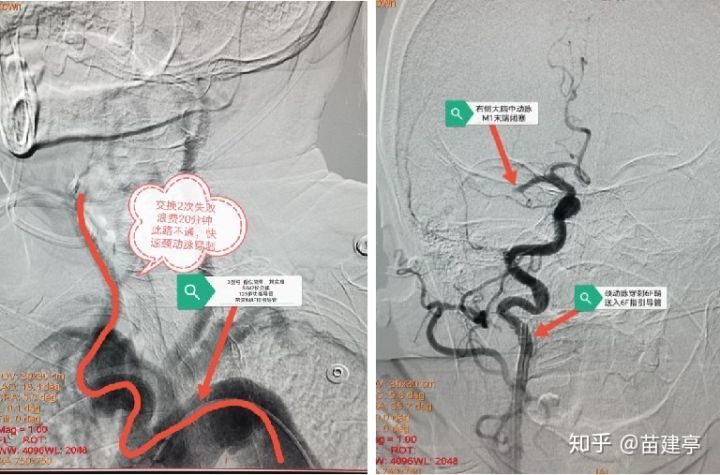

手术由张冬子执行院长带队、卒中中心李伟旺主任、陈斌副主任医师和杜乐乐住院总医师共同完成 。 造影显示“Ⅲ型弓” , 迂曲成角明显 , 交换技术无法将导管输送到位 。 危情时刻 , 脑组织濒临死亡 。 卒中团队讨论后 , 果断行颈动脉穿刺置鞘 , 之后行云流水般顺利将颅内血栓完全取出 , 快速恢复了颅内血流!术后30分钟患者肌力明显改善!之后使用专用血管封堵器完美封堵颈动脉穿刺点 。

右侧颈总动脉穿刺

抽吸导管到达闭塞点第一次抽吸